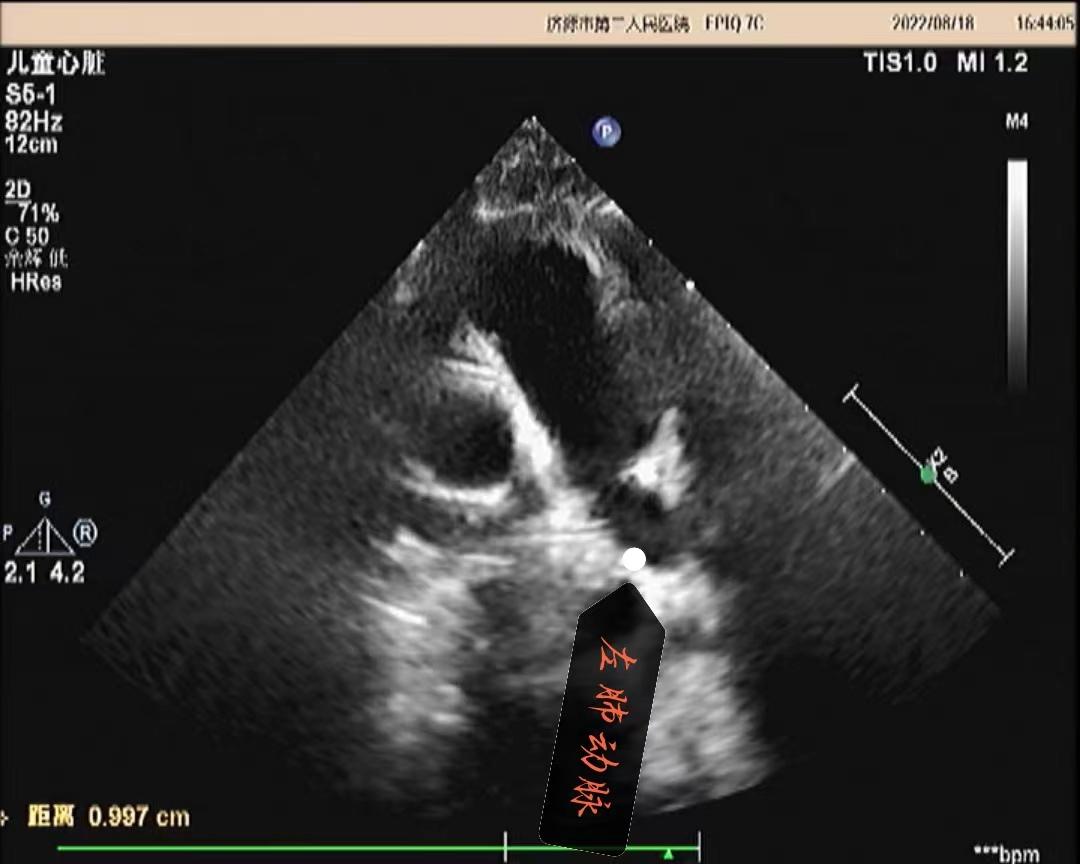

超声所见:各房室大小正常,肺动脉主干内径增宽,约20mm,左、右肺动脉内径分别约10mm、8.7mm,左、右肺动脉未见有狭窄,左肺动脉起始于主肺动脉的右侧并向左侧走行,右肺动脉起始于主肺动脉左侧向右走行。主动脉内径正常,搏动好。各瓣膜回声正常,肺动脉瓣开启可,关闭欠佳,余瓣膜启闭自如。房室间隔连续完整,室壁厚度及运动收缩幅度正常。CDFI:主肺动脉及左、右肺动脉前向流速增快。主肺动脉峰值流速:2.5m/s。左肺动脉峰值流速:2.2m/s。右肺动脉峰值流速:1.7m/s。肺动脉瓣口探及舒张期少量返流。

超声提示:1.左右肺动脉交叉 2.肺动脉主干内径增宽 3.肺动脉主干及左、右肺动脉前向流速增快 4.肺动脉瓣少量返流

(肺动脉主干及左肺动脉)